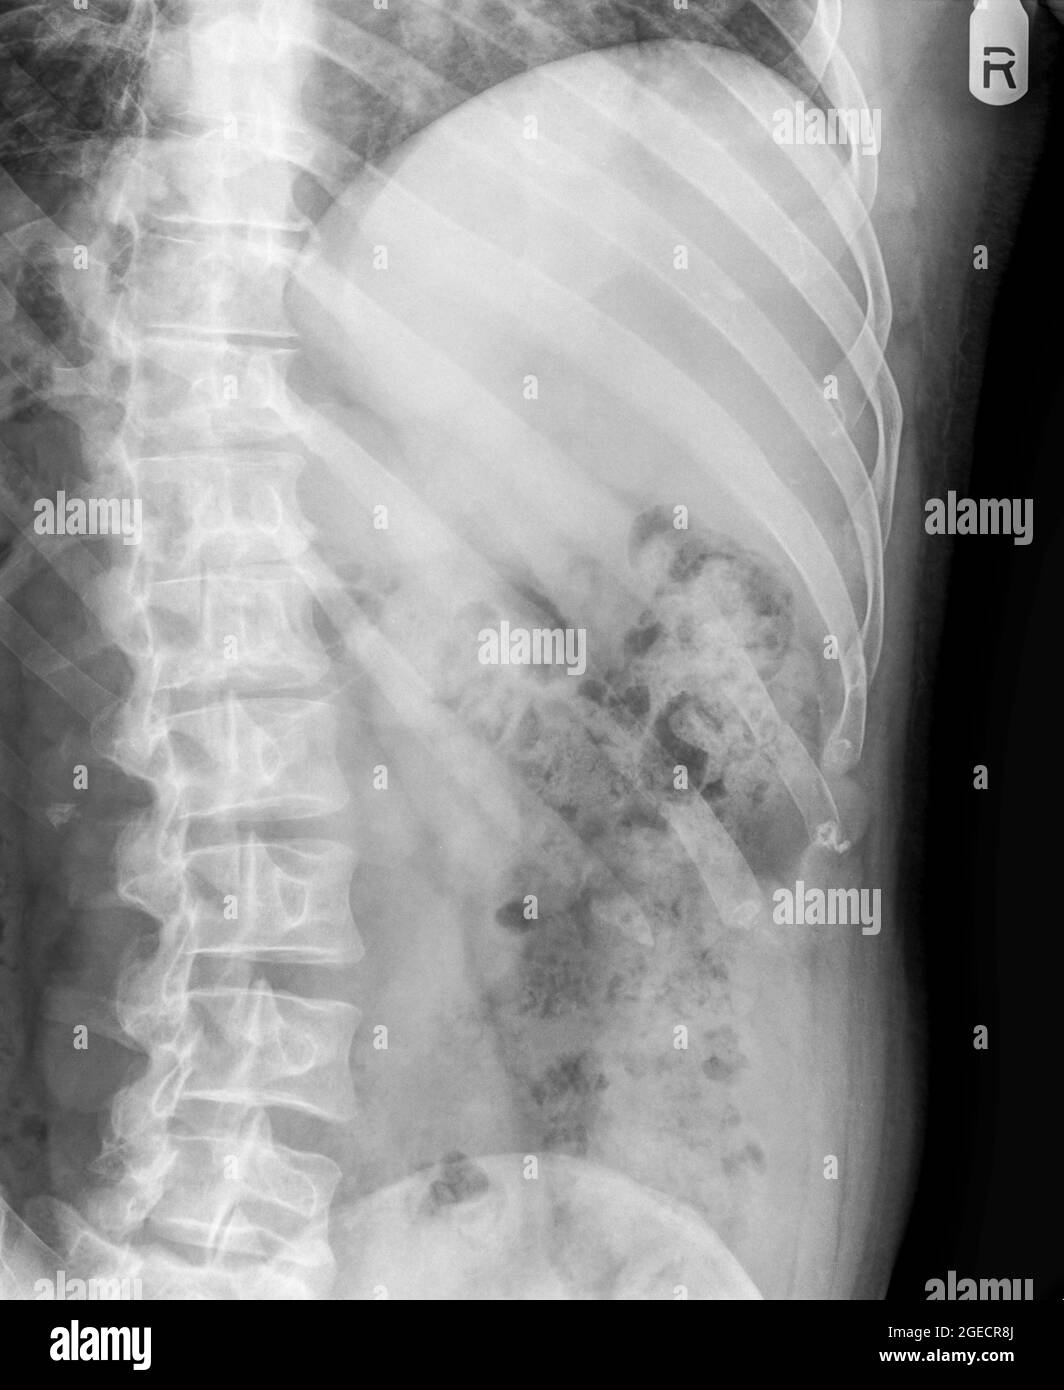

From www.alamy.com

Fractured rib x ray hires stock photography and images Alamy Can Broken Ribs Hurt Years Later But they don't cause the problems that ribs that have broken into pieces can. Broken ribs still hurt after 2 years is a medical condition where rib fractures take longer than usual to heal. The sharp edge of a. Pain in the chest area can persist for several weeks or. Prolonged chest wall pain is common, and the contribution of. Can Broken Ribs Hurt Years Later.